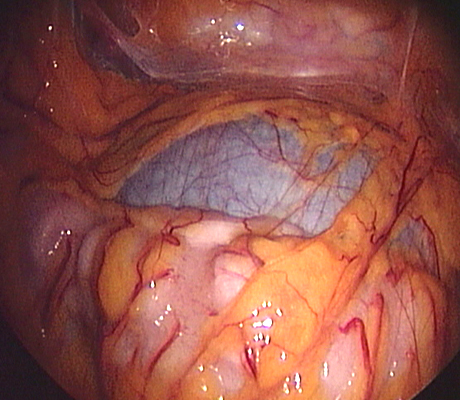

Examples of some pelvic masses dealt with by key-hole surgery.

Pelvic Mass